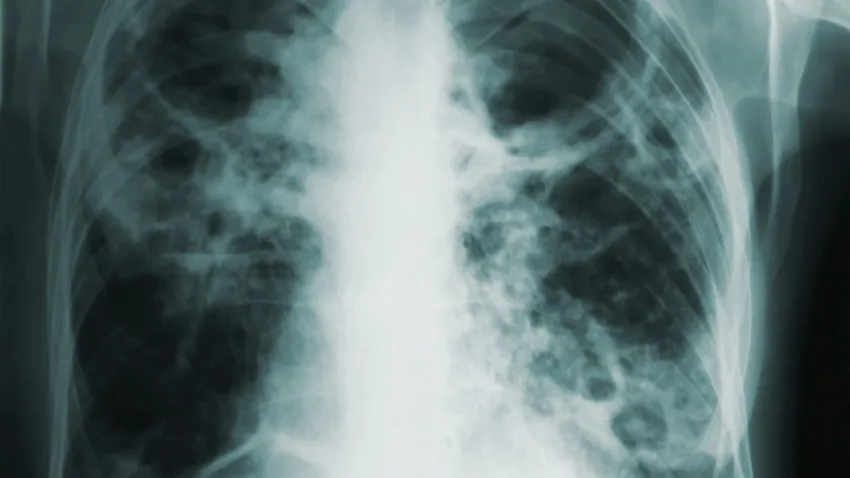

În contextul unei creșteri alarmante a cazurilor netratate sau diagnosticte tardiv, România continuă să se confrunte cu o situație dificilă în lupta împotriva tuberculozei, fiind unul dintre statele din Europa cu cele mai ridicate rate ale bolii. La nivel mondial, această boală infecțioasă rămâne o problemă majoră de sănătate publică, iar zilele de 24 martie devin un simbol al solidarității și al eforturilor globale de combatere a ei.

Este vital ca măsurile de prevenție să fie aplicate din timp, dat fiind faptul că, deși tuberculoza poate fi vindecată dacă este depistată devreme, recăderile sunt frecvente dacă boala nu este gestionată corespunzător. Acesta este și motivul acestei campanii, pentru a convinge populația să nu ignore simptomele și să se adreseze imediat medicului.

În fiecare an, ziua de 24 martie devine o platformă globală pentru conștientizare. Organizația Mondială a Sănătății estimează că, în 2021, aproximativ 4,1 milioane de oameni se află în situația de a nu fi fost încă diagnosticați oficial cu tuberculoză, un număr în creștere față de anul 2019, când se înregistraseră aproape 2,9 milioane de cazuri necunoscute. Această cifră arată amploarea subdiagnosticării și a subraportării, factorii majori care împiedică eradicaçãoea bolii.

În aceste condiții, mesajul zilei de luptă împotriva tuberculozei se concentrează pe necesitatea unui efort global de a intensifica screening-ul și accesul la tratament, dar și pe importanța prevenirii. Tuberculoza este o boală contagioasă, care poate fi tratată eficient dacă este identificată într-un stadiu incipient. Deși rezultatele tratamentului pot fi satisfăcătoare, imunitatea organismului nu rămâne neapărat întărită, ceea ce face ca revenirea bolii să fie o posibilitate reală.